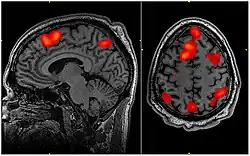

imagem por ressonância magnética funcional do cérebro com certas áreas em vermelho durante tarefas de memória de trabalho

imagem por ressonância magnética funcional do cérebro durante tarefas de memória de trabalho

O Fonoaudiólogo Especialista em Neuropsicologia está apto a prevenir, avaliar, tratar e gerenciar os distúrbios que afetam a comunicação humana e sua interface com a cognição, relacionando-a com o funcionamento cerebral.[25] Este profissional pode atuar na reabilitação das habilidades cognitivas que direta ou indiretamente se relacionam com a capacidade humana de se comunicar, trazendo de forma funcional ao dia a dia do paciente o uso dessas, por exemplo memorizar lista de compras, ir ao mercado, fazer as compras, paga-las e leva-las para casa, trabalhando habilidades como memória, planejamento e iniciativa.[27]